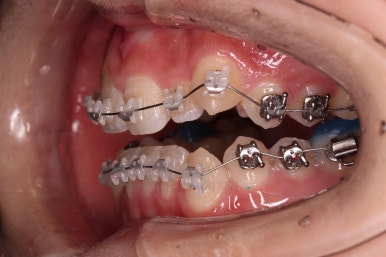

가벼운 철사에서 두꺼운 철사로 주기적으로 바꿔감에 따라 치열이 점점 가지런해지고 있습니다.

현재 모습도 나쁘지 않지만 좀 더 디테일을 맞춰주기 위해서 고무줄도 끼고, 왜소치 때문에 생기는 사이즈 부조화문제로 정중선이 안맞는 점은 일정 부분 수용하면서도 최대한 맞춰보기로 했습니다.

좀 더 디테일을 맞춰주고요.